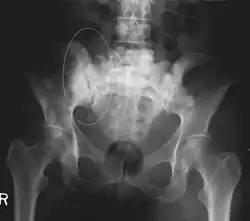

Sclerotic breast cancer metastases in the pelvis

Sources of bone metastases